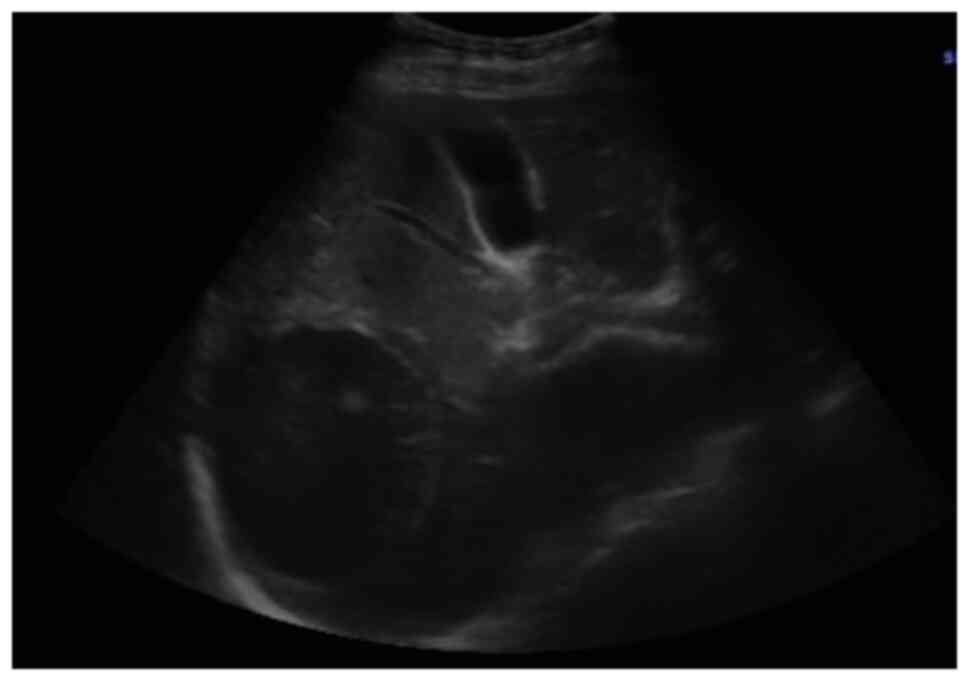

It was decided to perform PoCUS (LOGIQ e, GE Healthcare) following previously established protocols (6). A hypodense intrahepatic image was observed between segments VII and VI, with internal echoes suggestive of a liver abscess (Fig. 1). An ultrasound of the liver and bile ducts performed by a radiologist was requested. A well-defined hypodense lesion between segments VII and VI was confirmed, measuring 81x78x76 mm, with an approximate volume of 253 cc. He presented internal echoes, faint posterior acoustic enhancement and minimal perilesional vascular flow, findings that were associated with the clinical suspicion of liver abscess (Fig. 2). On the same day, radiology and general surgery were consulted. It was decided to perform tomography-guided percutaneous drainage of the liver abscess (IQon Spectral CT, Philips) following formerly recognized protocols (6). A 230 cc drainage was obtained, with no complications (Fig. 3, Fig. 4 and Fig. 5).

Figure 1

Point-of-care ultrasonography illustrating a hypodense intrahepatic image with internal echoes suggestive of an abscess.